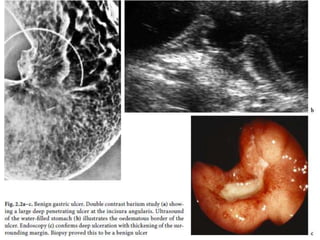

• Usually a little gas is present

in the stomach, which allows

the organ to be identified.

• When supine, a gas-filled

stomach can usually be

identified with the wall of the

greater curvature convex

caudally and the pyloric

antrum pointing cranially. It

is important to differentiate a

distended stomach from a

caecal volvulus, which may

also be positioned beneath

an elevated left

hemidiaphragm. Acute gastric dilatation after trauma